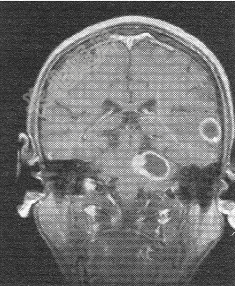

- 单项选择题患者男,72岁。肺癌术后一年余,现出现头晕头痛,MR图像如下,最有可能的诊断是

A、脑转移癌

B、脑膜瘤

C、脑胶质瘤

D、脑炎

E、脑淋巴瘤